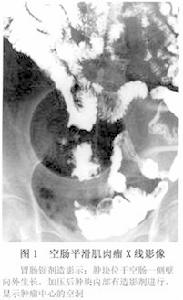

1.X線鋇劑造影 尤其是小腸插管氣鋇雙重造影檢查對診斷有一定幫助,腔內型的腫瘤檢查時較易發現。造影對十二指腸部位腫瘤診斷幫助較大,但對空迴腸腫塊由於腸袢盤曲影像重疊,一般的檢查方法不易發現病變。本病的X線表現可分為直接徵象及間接徵象:

(1)直接X線徵象:①腫瘤邊界清楚,兩端與正常腸壁之交角呈銳角,為圓形或橢圓形或結節樣;②正“3”或反“3”字征;③臍樣或牛眼樣龕影;④不規則隧道樣瘺管通向腸腔外的瘤體囊腔;⑤不規則的瘤體囊腔內鋇和(或)氣影,立位可見氣、液平面或氣、液、鋇三層陰影;⑥黏膜部分消失,部分呈弧形或橫形展開;⑦腫瘤軟組織影。

(2)間接徵象:①局部鋇劑通過快或呈鶒不同程度受阻;②局部腸腔變窄;③病變局部腸袢和/或周圍腸袢或器官受壓移位;④近端腸腔不同程度擴張;⑤偶有瘤體鈣化。